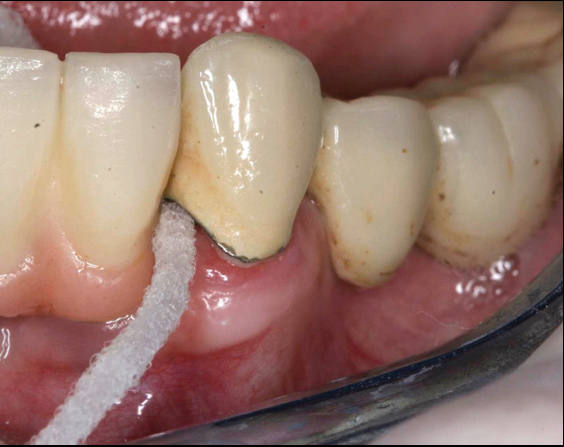

Fig 12. Treatment of peri-implantitis: peri-implant mucosal inflammation associated with plaque and calculus accumulation.

Figure 12

Fig 14. After removing the prosthesis, presence of peri-implant plaque and calculus.

Figure 14

Following a similar paradigm of treating peri-implantitis the same way that periodontitis is regularly successfully treated, based on the mechanical removal of biofilms adhered to implant/abutment surfaces, different protocols of nonsurgical implant debridement using different mechanical, physical, and chemical mechanisms have been evaluated (Figure 12 through Figure 15). In general, the use of different protocols combining treatments aimed to decontaminate the implant surface (eg, mechanical, lasers) and control the infection process (eg, antiseptics, antibiotics) have shown clinical and significant improvements in the commonly used surrogate outcomes (mean reductions in PPD of around 1.2 mm and mean reductions in the scores of BOP of about 50%) but have not resulted in disease resolution18 or a high degree of predictablility.19 There is currently no specific nonsurgical therapy that has shown efficacy in the resolution of peri-implantitis, and the clinical improvements reported in the clinical studies were not sufficient for the arrest of the disease, leaving the standard of care in the treatment of peri-implantitis as surgical in most cases.20